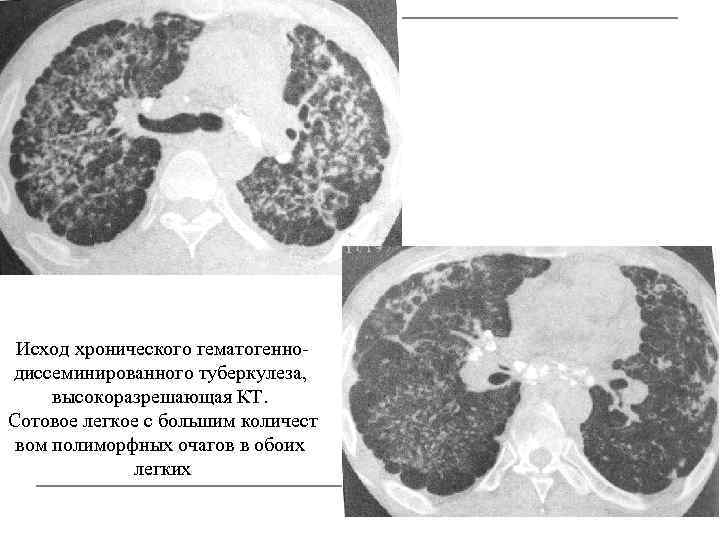

Исход хронического гематогеннодиссеминированного туберкулеза, высокоразрешающая КТ. Сотовое легкое с большим количест вом полиморфных очагов в обоих легких

КТ, срезы на разных уровнях.